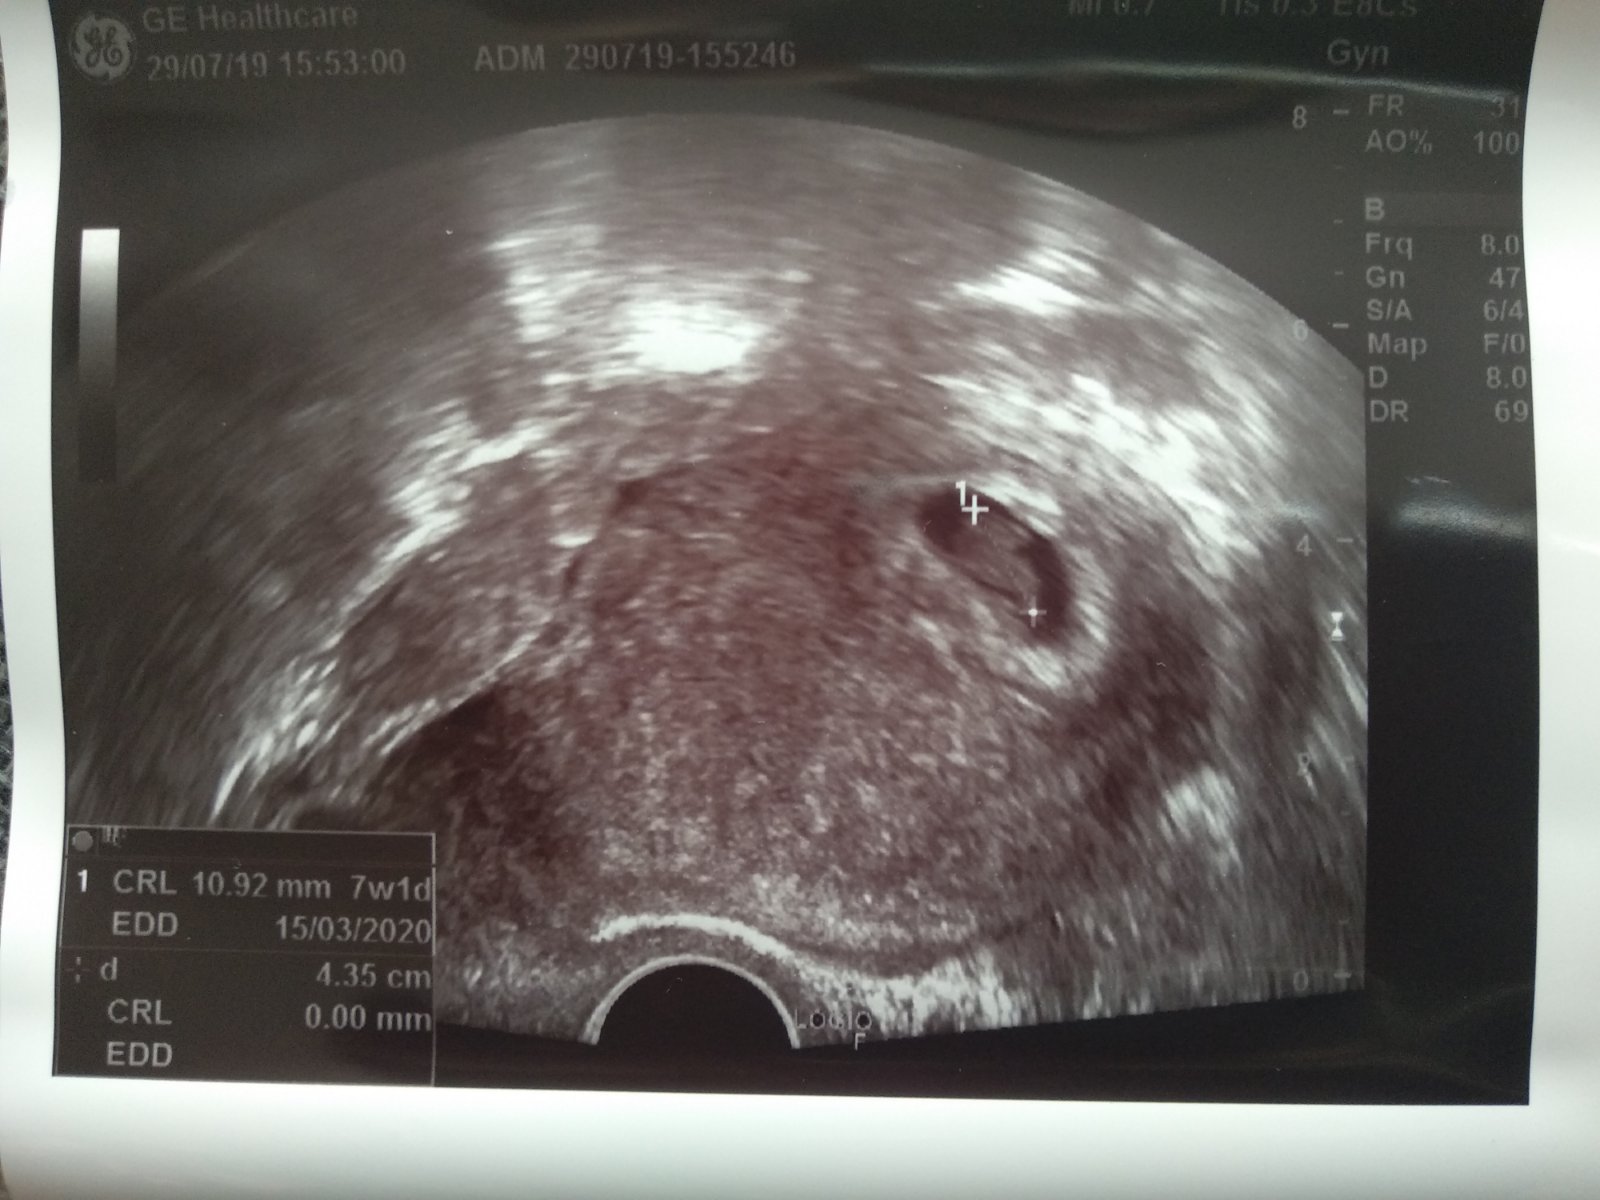

Ráda tu pokecám s někým kdo je na tom aktuálně podobně jaká já,nečekaný odchod miminka v 10tt a následná revize.Sdílet pocity i obavy ,těšení se na nové snažení a sdílení nadějí že se to už nebude opakovat,že zlé je vybrané.Já čekala páté miminko,neplánovaně a i jsem z kraje přemýšlela o potratu,než se mi vše po šoku urovnalo a miminko jsme přiali a neskutečně se těšili,i děti,vše šlo dobře až najednou na běžné kontrole miminku netlouklo srdíčko,prý se to stává,ale nikdo už vám neřekne jak těžké to bude a stále je,nikdy jsem neměla v těhotenství problémy,vždy zdravé a zdravým dítkem zakončené těhu,tohle mě tedy úplně semlelo.Dnes jsem 4 den po revizi a psychicky se zatím moc nezlepšuji......